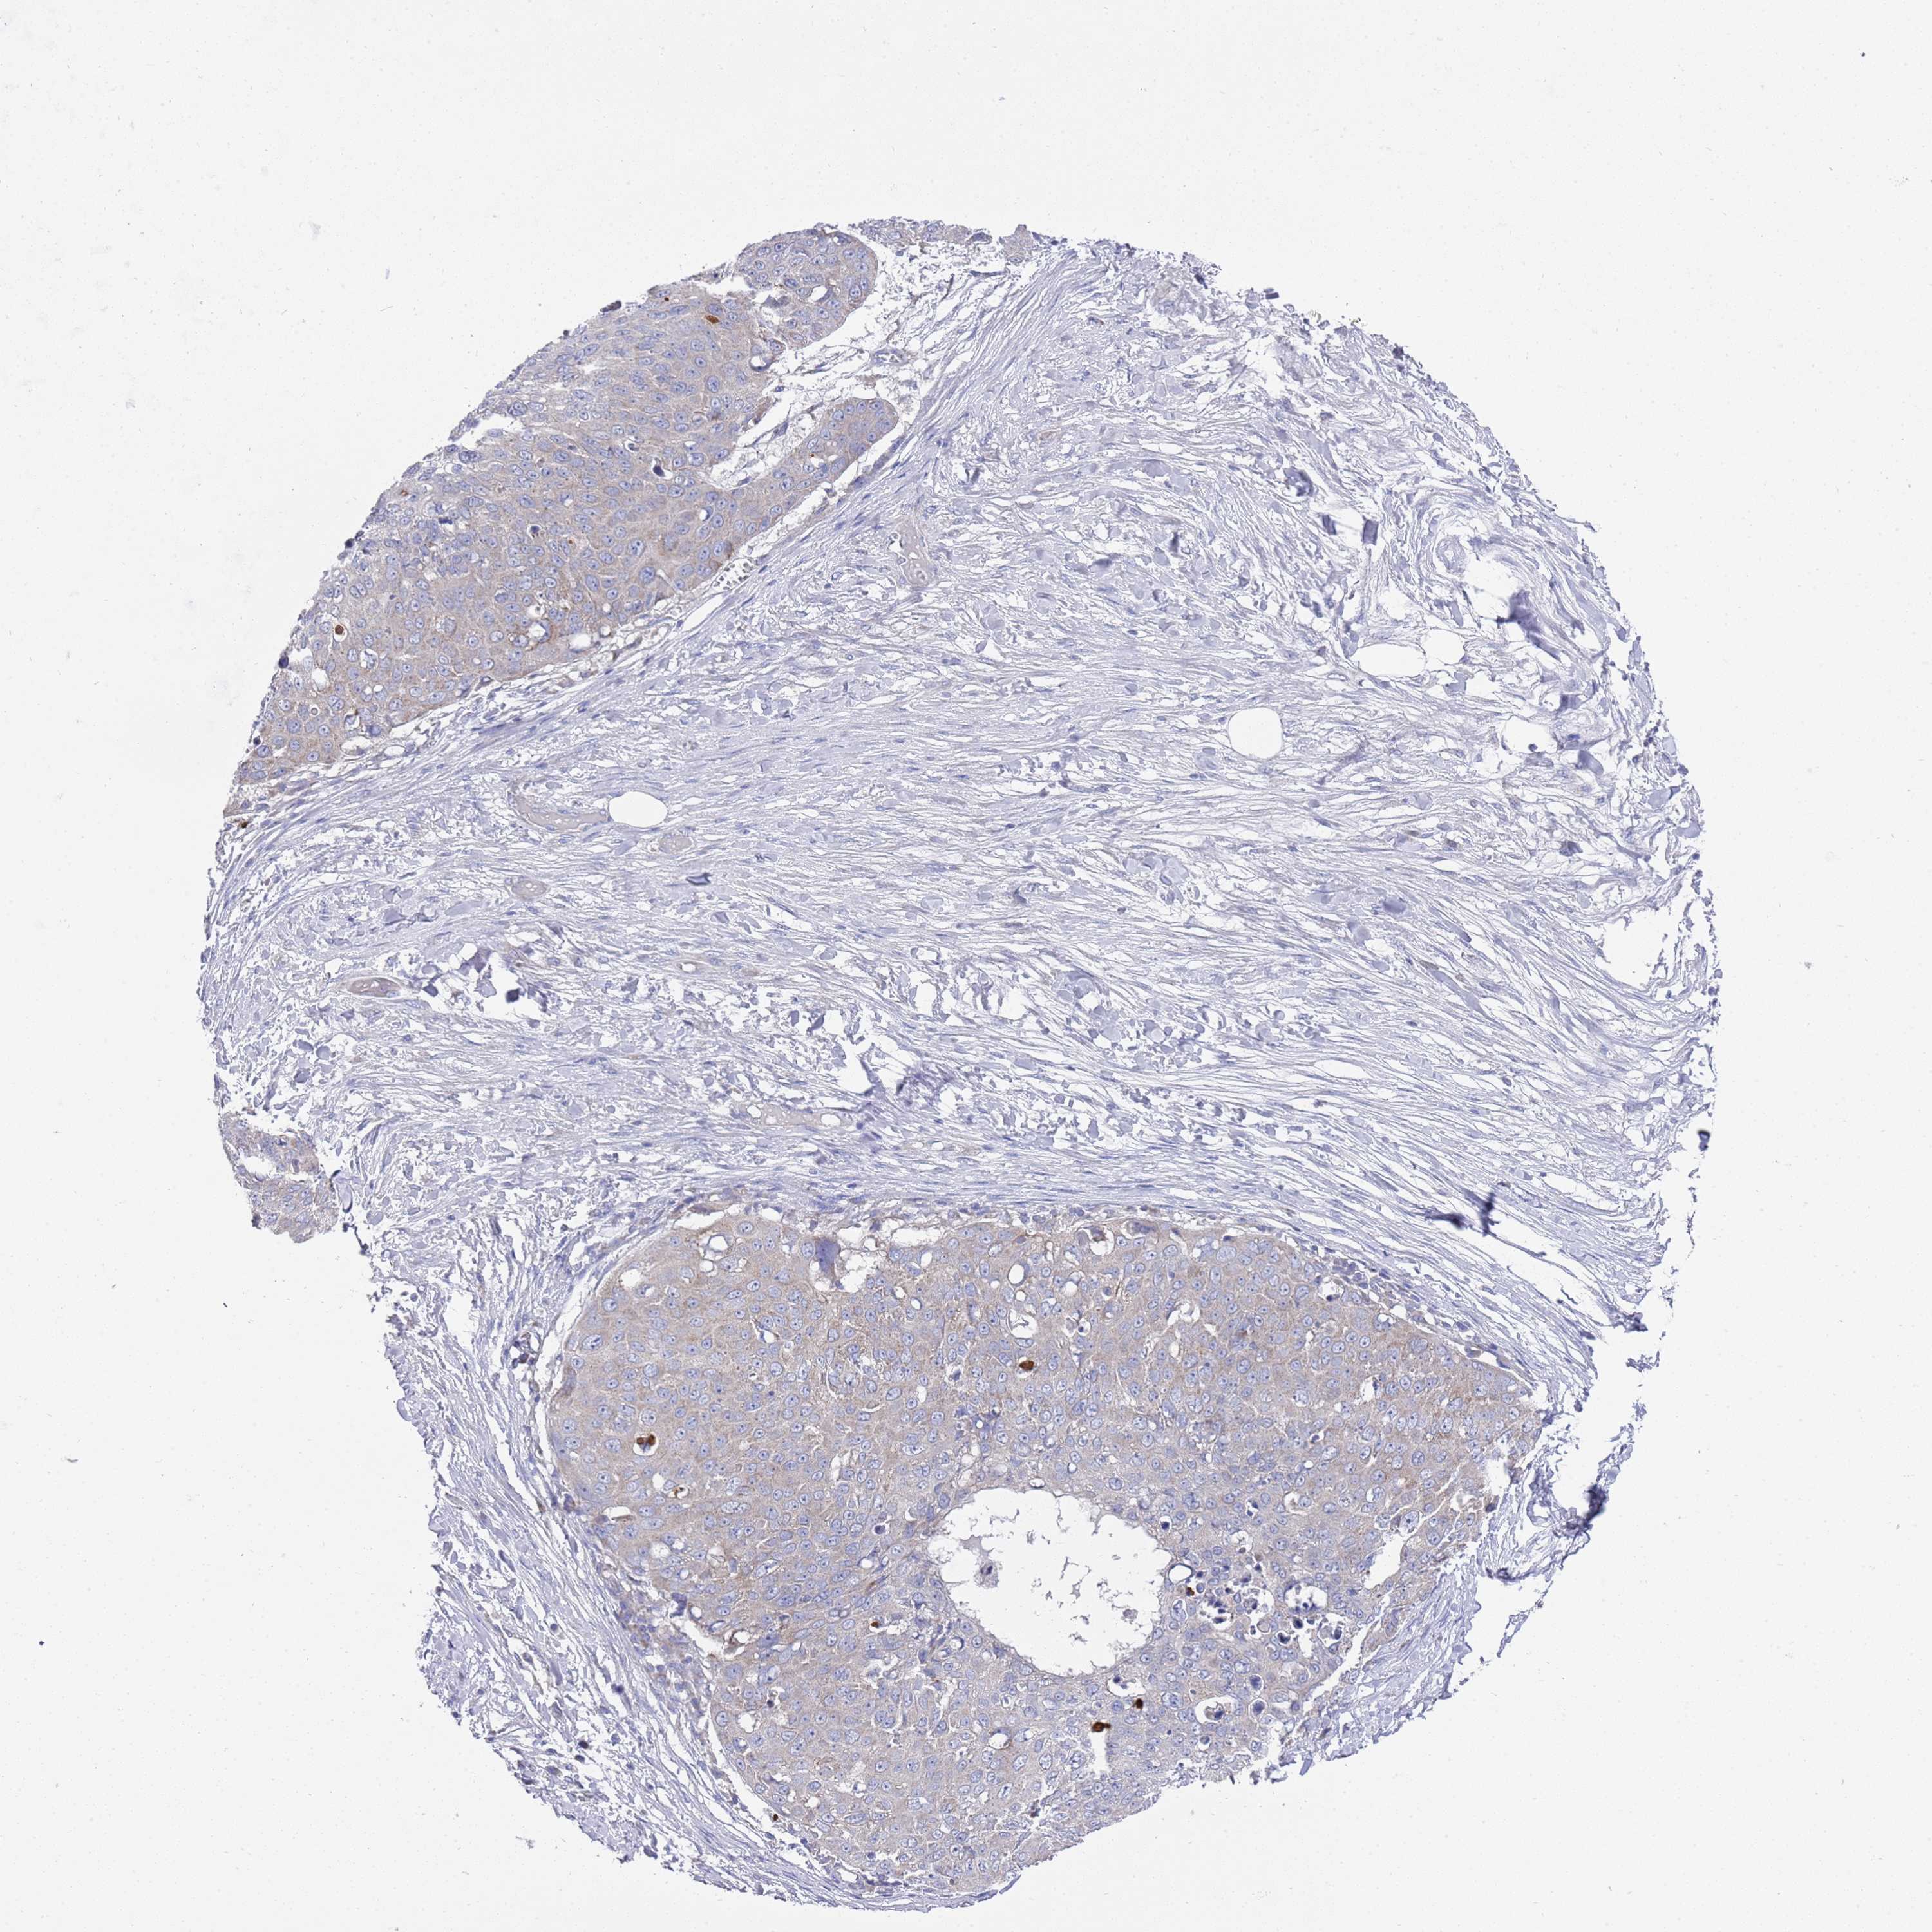

SKIN CANCER - Protein expressioni

A mouse-over function shows sample information and annotation data. Click on an image to view it in a full screen mode. Samples can be filtered based on level of antibody staining by selecting one or several of the following categories: high, medium, low and not detected. The assay and annotation is described here.

Each image is clickable and will lead to virtual microscopy that enables deeper exploration of all samples and also displays staining intensity scores, fraction scores and subcellular localization as well as patient and tissue information for each sample.

Antibody HPA021453

Squamous cell carcinoma, NOS